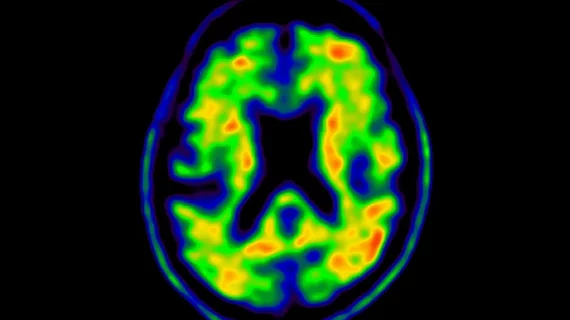

淀粉樣蛋白和tau PET成像使用標準十多年后首次更新

近日,美國核醫學和分子成像學會(SNMMI)與阿爾茨海默病協會合作,更新了淀粉樣蛋白和tau PET成像的適當使用標準(AUC)。這是自2013年制定輕度認知障礙患者的淀粉樣蛋白和tau成像標準以來,首次對該標準進行修訂。

此次更新之所以必要,是因為自AUC指南首次發布以來,阿爾茨海默病的研究和護理領域取得了顯著進展。新的核成像技術不斷涌現,同時,多種能夠減緩神經退行性疾病進展的治療方法也相繼獲得批準。此外,聯邦醫療保險和醫療補助服務中心還更新了淀粉樣蛋白和tau PET成像的報銷標準,使得這些檢查更加普及,成為診斷和治療阿爾茨海默病不可或缺的一部分。

SNMMI指導文件監督委員會主席Kevin Donohoe醫學博士在新聞稿中表示:“這些新標準旨在優化患者護理。它們將幫助醫療服務提供者確定這些重要PET示蹤劑的最有效用途,并明確哪些臨床情況下患者不太可能從PET成像中受益。AUC還討論了如何使用PET成像來確定新引入的癡呆癥治療的資格,以及跟蹤接受治療的患者對治療的反應。預計這些AUC還將減少對不太具體的診斷測試的需求,并為安全考慮提供指導。”

新的AUC定義了17種特定的臨床情況,以指導醫療服務提供者在哪些情況下進行成像“合適”、“不確定”或“很少合適”。具體而言,對于淀粉樣蛋白PET,一個多學科專家團隊確定了七種適合進行檢查的情況,兩種情況使用不確定或值得懷疑,八種情況不適合進行檢查;對于tau成像,該團隊認為有五種臨床情況適合進行檢查,六種情況不確定,另外六種情況很少合適。

在制定這些新標準時,專家們綜合考慮了患者的年齡、病史、腦脊液生物標志物、癥狀以及預后情況,同時還考慮了阿爾茨海默病和其他癡呆癥特有的個體風險因素。